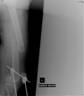

Removal of fixator and immediate exchange unreamed AO solid femur nail inserted by closed meanns

Results

Good bony union and alignment with fracture well reduced